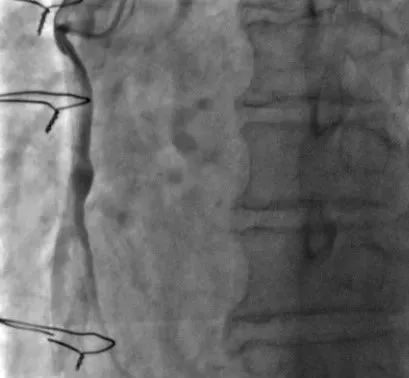

75岁的李先生在20年前行冠状动脉搭桥手术,撘了3根桥。近2年反复胸闷胸痛发作,最近3月症状加重,快走或上楼后就会出现明显的胸痛伴背痛,就诊于我院心内科。行冠状动脉造影检查,可以看到冠状动脉原有的三根血管前降支,回旋支,右冠状动脉均有弥漫性的狭窄阻塞:右冠状动脉远端闭塞,前降支的乳内动脉桥,回旋支的大隐静脉桥血管通畅,但右冠状动脉桥血管远端吻合口闭塞且伴有血栓形成,可见右冠桥血管内明显的造影剂滞留。

经过充分的准备,在心内科主任刘巍教授的指导下,介入经验丰富的术者心内科主范军任医师和助手兰永昊医生对静脉桥血管进行介入治疗。考虑桥血管病变的特殊性,尤其是静脉桥血管,盲目扩张很容易导致更严重的并发症出现。仅从造影来看,无法完全明确桥血管内病变性质特点,在导丝通过闭塞血管段后,使用血管内超声进行检查可见到,桥血管远端吻合口部位为纤维组织增生为主,桥血管内无明显血栓。然而球囊扩张吻合口时由于病变坚硬,多次出现球囊滑脱难以扩张成功,刘巍与范军根据病变特点,决定在准分子激光对桥血管进行充分消蚀的基础上,再次扩张血管。激光消蚀后,血流明显改善,狭窄程度也有减轻,之后再次使用球囊扩张可见扩张效果非常满意,基本无残余狭窄,植入药物球囊,未植入支架,最终效果非常满意。